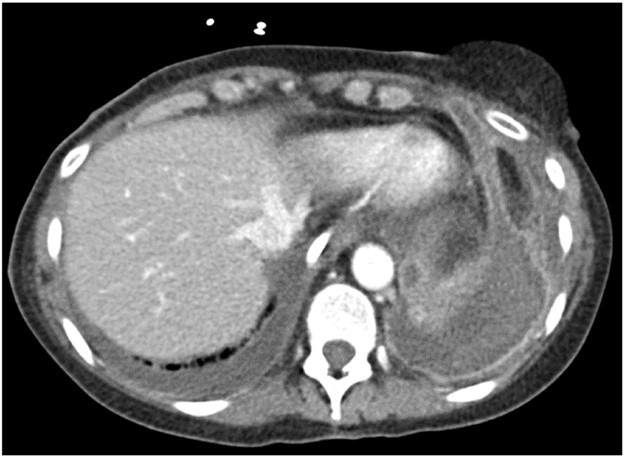

PE can occur after lung transplant. Hemorrhage most commonly occurs during the immediate and early postoperative periods and can manifest as hemothorax, other forms of thoracic hemorrhage such as mediastinal hematoma and chest-wall hematoma, and nonthoracic hemorrhage such as retroperitoneal hematoma. Approximately 4.5% of lung transplant recipients experience posttransplant hemorrhage severe enough to require surgical intervention [7]. The causes of hemorrhage include inadequate coagulation, vascular anastomotic dehiscence (which is rare but can be catastrophic when it occurs), and injury of other vessels. CT of the body part of concern (for example, CT of the chest if there is concern for mediastinal hemorrhage) should be performed, ideally with IV contrast material. If active hemorrhage is suspected, CT can be performed before and after the administration of IV contrast material in the arterial and venous phases to detect contrast material extravasation.

The imaging findings of hemorrhage and PE are the same in lung transplant recipients as in nontransplant patients. Hemorrhage manifests as hyperattenuating fluid (higher attenuation than that of simple fluid) or a hyperattenuating mass (if it is a hematoma) that often has a heterogeneous appearance. PE manifests as hypoattenuating and well-defined filling defects in the contrast material–opacified pulmonary artery branches. These filling defects can be occlusive or nonocclusive; nonocclusive acute PE is centrally located in the vessel lumen, rather than eccentric. Patients with coagulopathy and patients who are receiving anticoagulation therapy for DVT or PE may have both hemorrhage and PE on imaging. Figure 6 shows a patient with bilateral chest-wall hematomas.